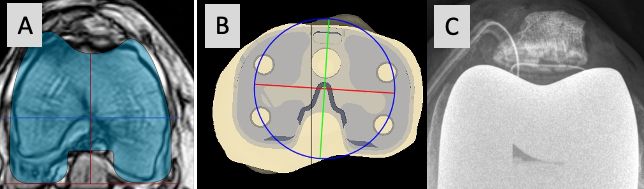

Some surgeons recommend to routinely perform 3-D analysis before surgery, and this is mandatory for surgeons using patient specific cutting blocks and robotic surgery. This 3-D planning allows not only to identify any axial plane deformity of the femur and tibia before surgery but also makes proper correction during surgery easier and more reproducible. We do not routinely plan the axial plane with CT or MR imaging. History, clinical examination and axial weight bearing patella views are routinely used to identify any patella maltracking or asymmetric flexion gap. Only in cases with complex patella dislocations, we perform a rotational profile with MR imaging, to identify where the axial plane deformity is located (femur, tibia or both) (Fig 14).

Some surgeons recommend to routinely perform 3-D analysis before surgery, which allows not only to identify any axial plane deformity of the femur and tibia before surgery but also makes proper correction during surgery easier and more reproducible [7]. We do not routinely plan the axial plane with CT or MR imaging. Only in cases with complex patella dislocations, we perform a rotational profile of the knee with MR imaging, to identify where the axial plane deformity is located (distal femur, proximal tibia or both) (Fig 14).

In our experience we use this technique in young patients with native knees only, but it was never necessary for TKA patients. In these severe tibial axial deformities, a combination of PS or CCK constraint, TT osteotomy, lateral retinaculum release and proximal realignment can correct the deformity. Combined with the correction of the distal femur axial plane deformity inside the joint this will produce proper patella tracking even in patients with permanent patella dislocation before surgery (Fig 14 and 27).